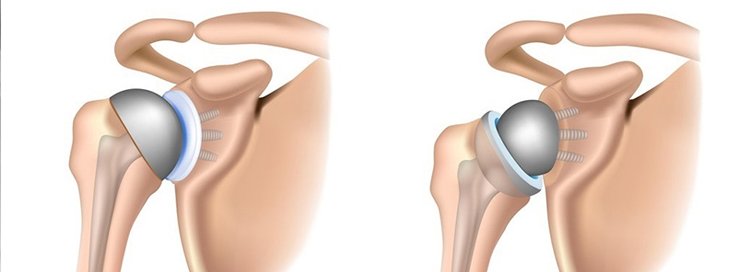

1. Total Shoulder Replacement – Replaces both the ball (humeral head) and socket (glenoid).

2. Partial Shoulder Replacement – Only the humeral head is replaced.

3. Reverse Shoulder Replacement – Used for rotator cuff tear arthropathy, where the ball and socket positions are reversed.